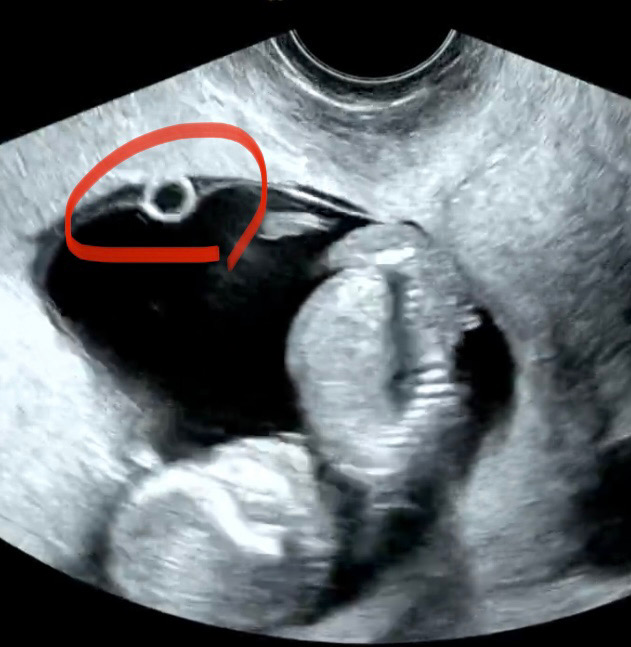

안녕하세요! 11주 6일차 땡큐(태명) 아빠에요! 오늘 일요일에 진료 볼 수 있는 병원이 근거리에 있어서 한번 다녀왔네요. 오늘 진료볼 땐 못 봤다가 받은 영상을 쭉 보다보니 아기집과 양막 사이에 동그란게 잡혔는데 뭔지 감이 전혀 오질 않네요~ 혹시 아시는 분이 계실까요?? 궁금하네요ㅠ

난황이요 ~~산과에서 보시면서 설명해주셔서 저도 알았어요 ㅎㅎㅎㅎ 난황이 있어야 영양분도 챙기며 건강히 잘 있다는거래요~~ㅎㅎㅎ

난황이요 아직은 난황으로 엄마영양분을 먹고있어서그럴꺼예요

난황같아요!